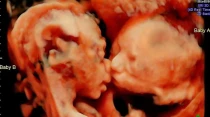

Las gemelas Isabella y Callie compartiendo un gesto de cariu00f1o en el vientre / Foto: Instagram Carissa Gill

FOTO VIRAL: Ecografía capta a gemelas dándose un tierno beso en el vientre materno

Apr 17, 2017

Por María Ximena Rondón

Una mujer estadounidense con 25 semanas de embarazo descubrió algo curioso cuando fue a realizarse una ecografía: vio a sus... Leer más